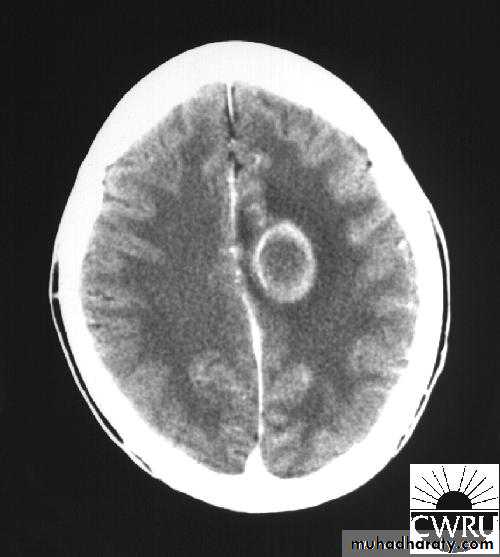

Brain Abscess CT with contrast